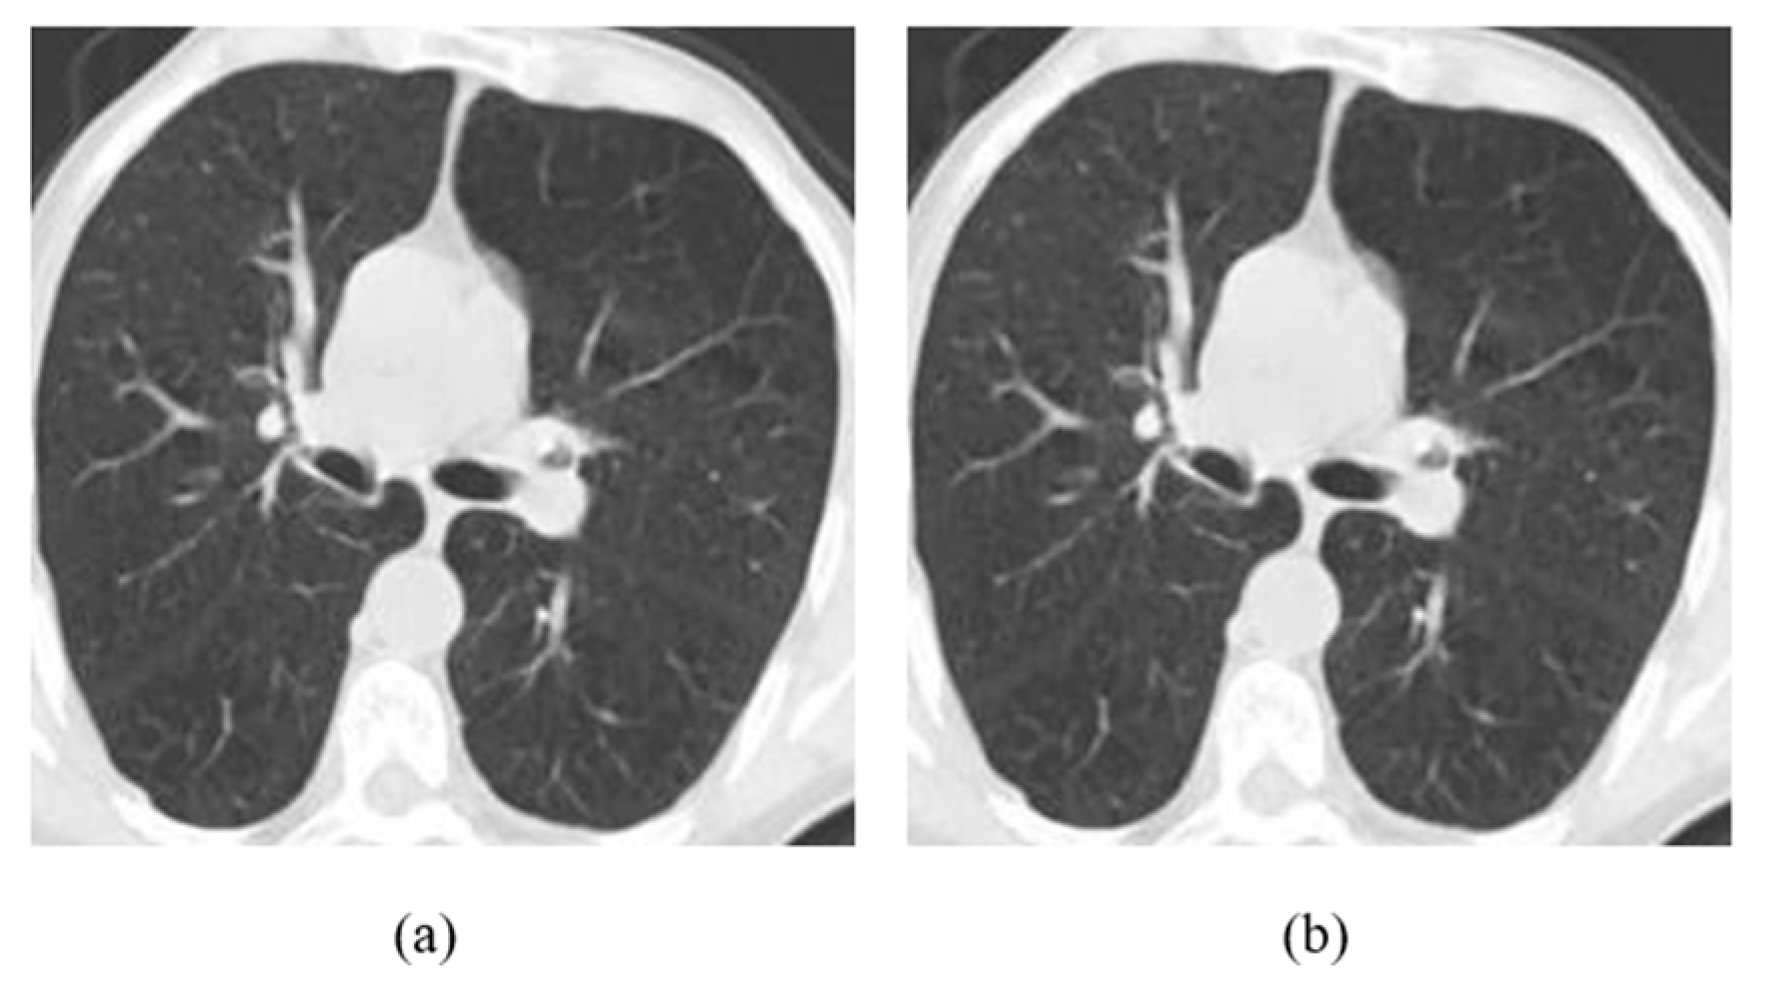

4.1. Datasets

4.2. Ablation Study

4.3. Results